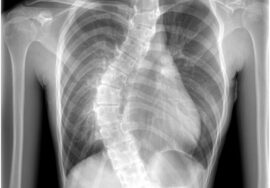

الجنف هو انحناء غير طبيعي في العمود الفقري يحدث عادة على شكل حرف “C” أو “S”، ويُعد من الحالات الشائعة لدى الأطفال والمراهقين، خاصة في فترة النمو السريع بين عمر 10 و15 عامًا. ورغم أنه قد يصيب أي فئة عمرية، إلا أن اكتشافه المبكر يلعب دورًا مهمًا في العلاج والوقاية من المضاعفات.

الأشعة السينية (X-ray): تُستخدم لقياس زاوية الانحناء بدقة (زاوية كوب).